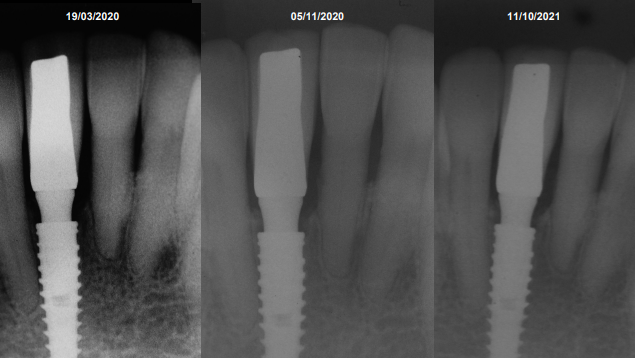

Após 35 dias da instalação do implante foi realizada a abertura do implante através de um bisturi circular e o pilar Ideale reto de 3.3 X 4.0 X 2.5 mm foi torqueado no implante a 20 Ncm. Foi realizada também uma moldagem deste pilar com o seu transferente correspondente e a prótese adesiva voltou a ser instalada. Depois de uma semana, o provisório parafusado confeccionado no laboratório foi instalado e mantido em posição durante 15 dias para formar um novo perfil de emergência, aproximando as características dos tecidos circundantes às características de um incisivo central inferior. Neste momento, foi realizada uma nova moldagem da região e uma coroa metalocerâmica foi confeccionada e instalada após uma semana. Foi também realizada a radiografia.

O resultado clínico alcançado com sucesso foi fruto das escolhas corretas durante o planejamento cirúrgico/protético e somente apresentou essas características clinicas de naturalidade por ser uma conexão Cone Morse e por ter um pilar protético mais estreito do que o diâmetro do implante.